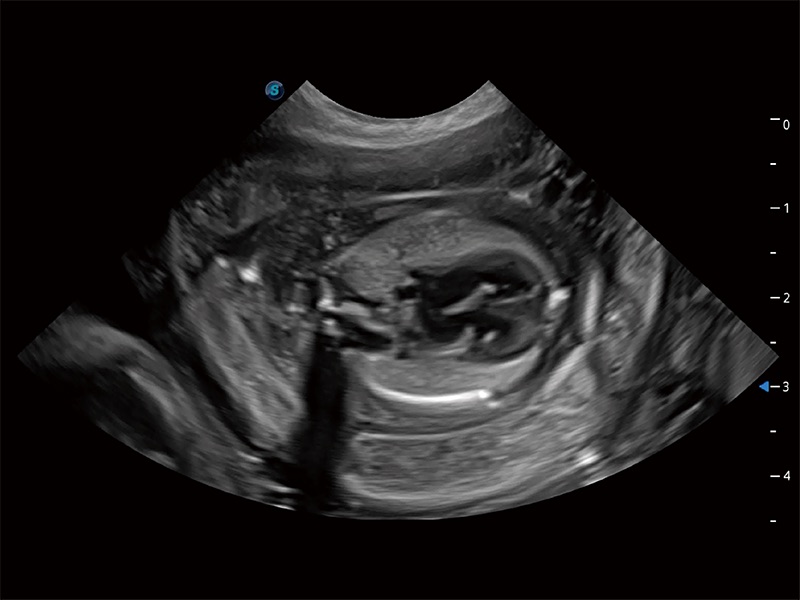

一键自动识别膀胱壁及自动测量膀胱容积,不受膀胱形状和大小的限制,帮助医生快速精准获得测量的数据。

ProPet 80 全新的动物超声智能软件和丰富的探头群,为动物医生提供了高清晰度和精细分辨率的图像,无论在宠物、马科、畜牧还是实验室动物等应用中都可以轻松应对,为您的日常工作带来满意的体验。